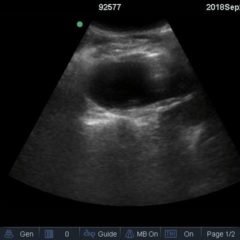

Point-of-care cardiac echocardiogram demonstrated a dilated ascending aorta (illustrated in red) measuring approximately 4 cm in the parasternal long axis (PLAX). A dilated aortic arch (illustrated in green) also measuring approximately 4 cm was appreciated using the suprasternal notch view (SSNV). A follow-up computed tomography angiogram (CTA) was performed, validating bedside ultrasound measurements.

The diagnostic criteria for dilated thoracic aneurysm is based on multiple factors including age, sex, and body size.2 An aortic root diameter of ³ 4.0 cm constitutes an ascending aortic dilation.3,4 Point-of-care cardiac and SSNV ultrasound of the thoracic aorta has been validated as an accurate study when performed by emergency physicians to identify thoracic aortic aneurysms (sensitivity of 71.4%, specificity of 100% when compared to gold standard of CTA). 5 This case is an example of the utility of rapid bedside diagnostic ultrasound, specifically the SSNV, in assessment of thoracic aneurysms.